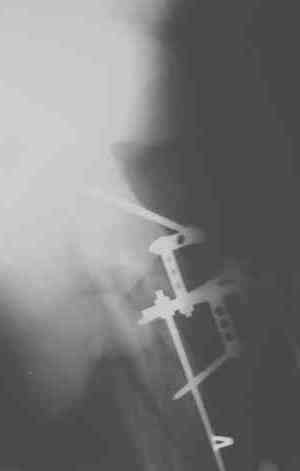

Уважаемые коллеги! Пришел на консультацию вот такой больной (первые 3-и рисунка). Травма автодорожная, апрель 2006г. Лечился консервативно, вытяжение и гипс. Через пять месяцев стал ходить. Укорочение бедра 6 см. 26 февраля 2007г. оступился, упал. Прооперирован в г.Баку - наложен стержневой аппарат. Ходит с костылями, наступая на левую ногу. Мы попросили что нибудь из ранних снимков. Принес рентгенограммы перелома (рис. 4,5). Посмотрели, наснимали сами (рис. 6-10). Похоже, что нет сращения нигде. Хотелось - бы обсудить следующие вопросы:1. дальнейшая тактика - реостеосинтез или подождать (ослабить аппарат, дать нагрузку и т.д.)?2. если реостеосинтез - то чем и как? Юрий Алексеевич Булахтин

Юрий Алексеевич. Привет. А сустав тазобедренный живой? На одном из снимков он возник - но качество рентгенограммы - швах. Если он жживой то я бы сделал

гвоздь с блокированием, через некоторое время после снятия аппрата, вмешиваясь на больших углах малоинвазивно. А если нет.....То стоит подумать

об ТHR с очень длинной ножкой. А Рыков. Хабаровск.

Спасибо за участие в обсуждении случая. Тазобедренный сустав сохранный.